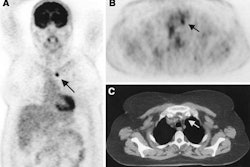

The U.S. Centers for Medicare and Medicaid Services (CMS) has published a new tracking sheet announcing the acceptance for five formal requests for a National Coverage Determination (NCD) on the use of FDG-PET imaging for brain, cervical, pancreatic, small cell lung, and testicular cancers. The CMS is commissioning a single Technology Assessment to address all five coverage requests. The current tentative due date for completion of the review of the NCD request is September 1, 2003.